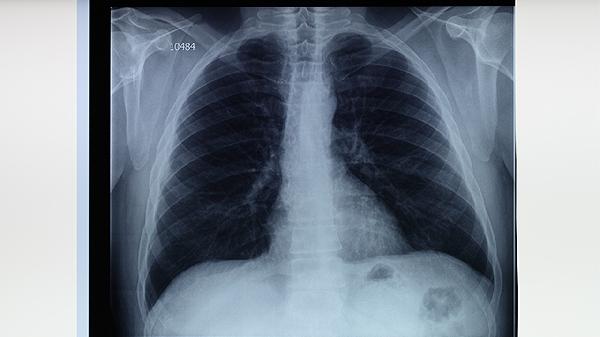

肺結(jié)核病的飲食調(diào)養(yǎng)原則主要有保證優(yōu)質(zhì)蛋白攝入、補(bǔ)充維生素和礦物質(zhì)、選擇易消化食物、避免刺激性食物、保持規(guī)律飲食等。合理的飲食有助于改善營(yíng)養(yǎng)狀況,增強(qiáng)機(jī)體抵抗力,促進(jìn)疾病康復(fù)。